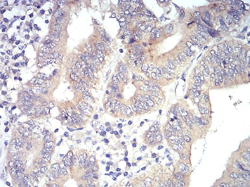

IHC    1/200 - 1/1000